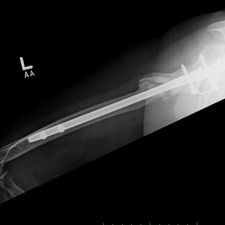

She was advised of the need to do some sort of stabilization which is necessary since the use of low-dose ultrasound has not helped in the healing process. She was unwilling to have any further operative intervention and sought further options. Eventually, she agreed to a fourth procedure of intra-medullary nail stabilization of the fracture and had this carried out in April 2011. An intramedullary nail was inserted in an antegrade manner and she has since gone on to heal the fracture site completely and has regained most of the function of the upper limb with no pain.

This case illustrates the possible complications that can occur with any surgery but also our commitment to our patients by sticking with them and making sure that a positive outcome is had despite the many challenges that may arise.